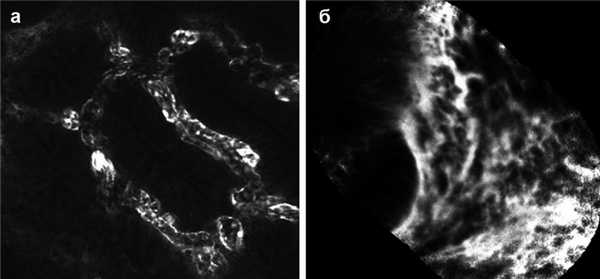

Конфокальная лазерная эндомикроскопия

Методика конфокальной лазерной эндомикроскопии применяется с 2004 г. Она позволяет увидеть СО кишечника in vivo в реальном времени при 1000-кратном увеличении во время эндоскопии [13]. В настоящее время имеются два устройства, разрешенных к применению Администрацией США по контролю за лекарственными препаратами и пищевыми продуктами - FDA (рис. 5). Рисунок 5. Конфокальная лазерная эндомикроскопия с использованием встроенного (iCLE, а) либо автономного (рCLE, б) зондов. Выявляются расширенные микрососуды, повышенная сосудистая проницаемость и нарушенная структура крипт при активном язвенном колите. Одно устройство встраивается в дистальный наконечник эндоскопа высокого разрешения (iCLE, Pentax, Токио, Япония), а другое представляет собой автономный зонд, свободно проходящий через рабочий канал большинства стандартных эндоскопов (pCLE, Cellvizio, Mauna Technologies, Париж, Франция). Лазерный источник синего света генерирует возбуждающее излучение с длиной волны 488 нм, а отраженный свет определяется на волне >505 нм. При эндомикроскопии требуется применение системных (флуоресцеин) либо топических (акрифлавин, крезиловый фиолетовый) флуоресцентных красителей [14].

О. Watanabe и соавт. [15] сравнивали эндомикроскопическую картину воспаленной и невоспаленной СО прямой кишки у 17 больных НЯК и у 14 человек контрольной группы. Конфокальные изображения сопоставляли с данными обычного гистопатологического исследования. Эндомикроскопия позволяла визуализировать структуру крипт, капилляров и воспалительных клеток, давая такую же информацию, как гистопатологические методы.

Недавно предложена новая классификация воспалительной активности при НЯК на основании данных эндомикроскопических исследований [16], включая архитектонику крипт и микрососудистые изменения. Авторы продемонстрировали надежность эндомикроскопической оценки воспалительной активности в реальном времени у больных НЯК и достоверную корреляцию ее изменений с гистологическими изменениями (в обоих случаях р

Мы предприняли оценку пригодности эндомикроскопии для выявления in vivo изменений, ассоциирующихся с БК. Используя зонд pCLE, мы показали, что эндомикроскопия позволяет с высокой точностью определять изменения, ассоциирующиеся с БК. Более того, pCLE с такой же точностью, как гистологическое исследование (0xEA;=0,8, неопубликованные данные), позволяла выявлять остаточное макроскопическое невидимое воспаление СО.